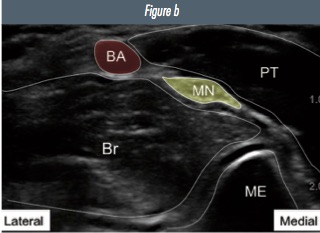

Identify the brachial artery (pulsatile anechoic). The median nerve lies medial to the artery as a distinct hyperechoic structure. It is oval shaped, at a varying distance 0.5–2 cm from the artery. It is seen lateral and deep to pronator teres muscle. The ‘peak’ of the medial epicondyle of the humerus can be seen medially.

Figure 2: a) ultrasound image of the median nerve and surrounding structures in the antecubital fossa b) annotated image (BA=brachial artery; MN=median nerve; PT=pronator teres muscle; Br=brachialis muscle; ME=medial epicondyle of humerus).